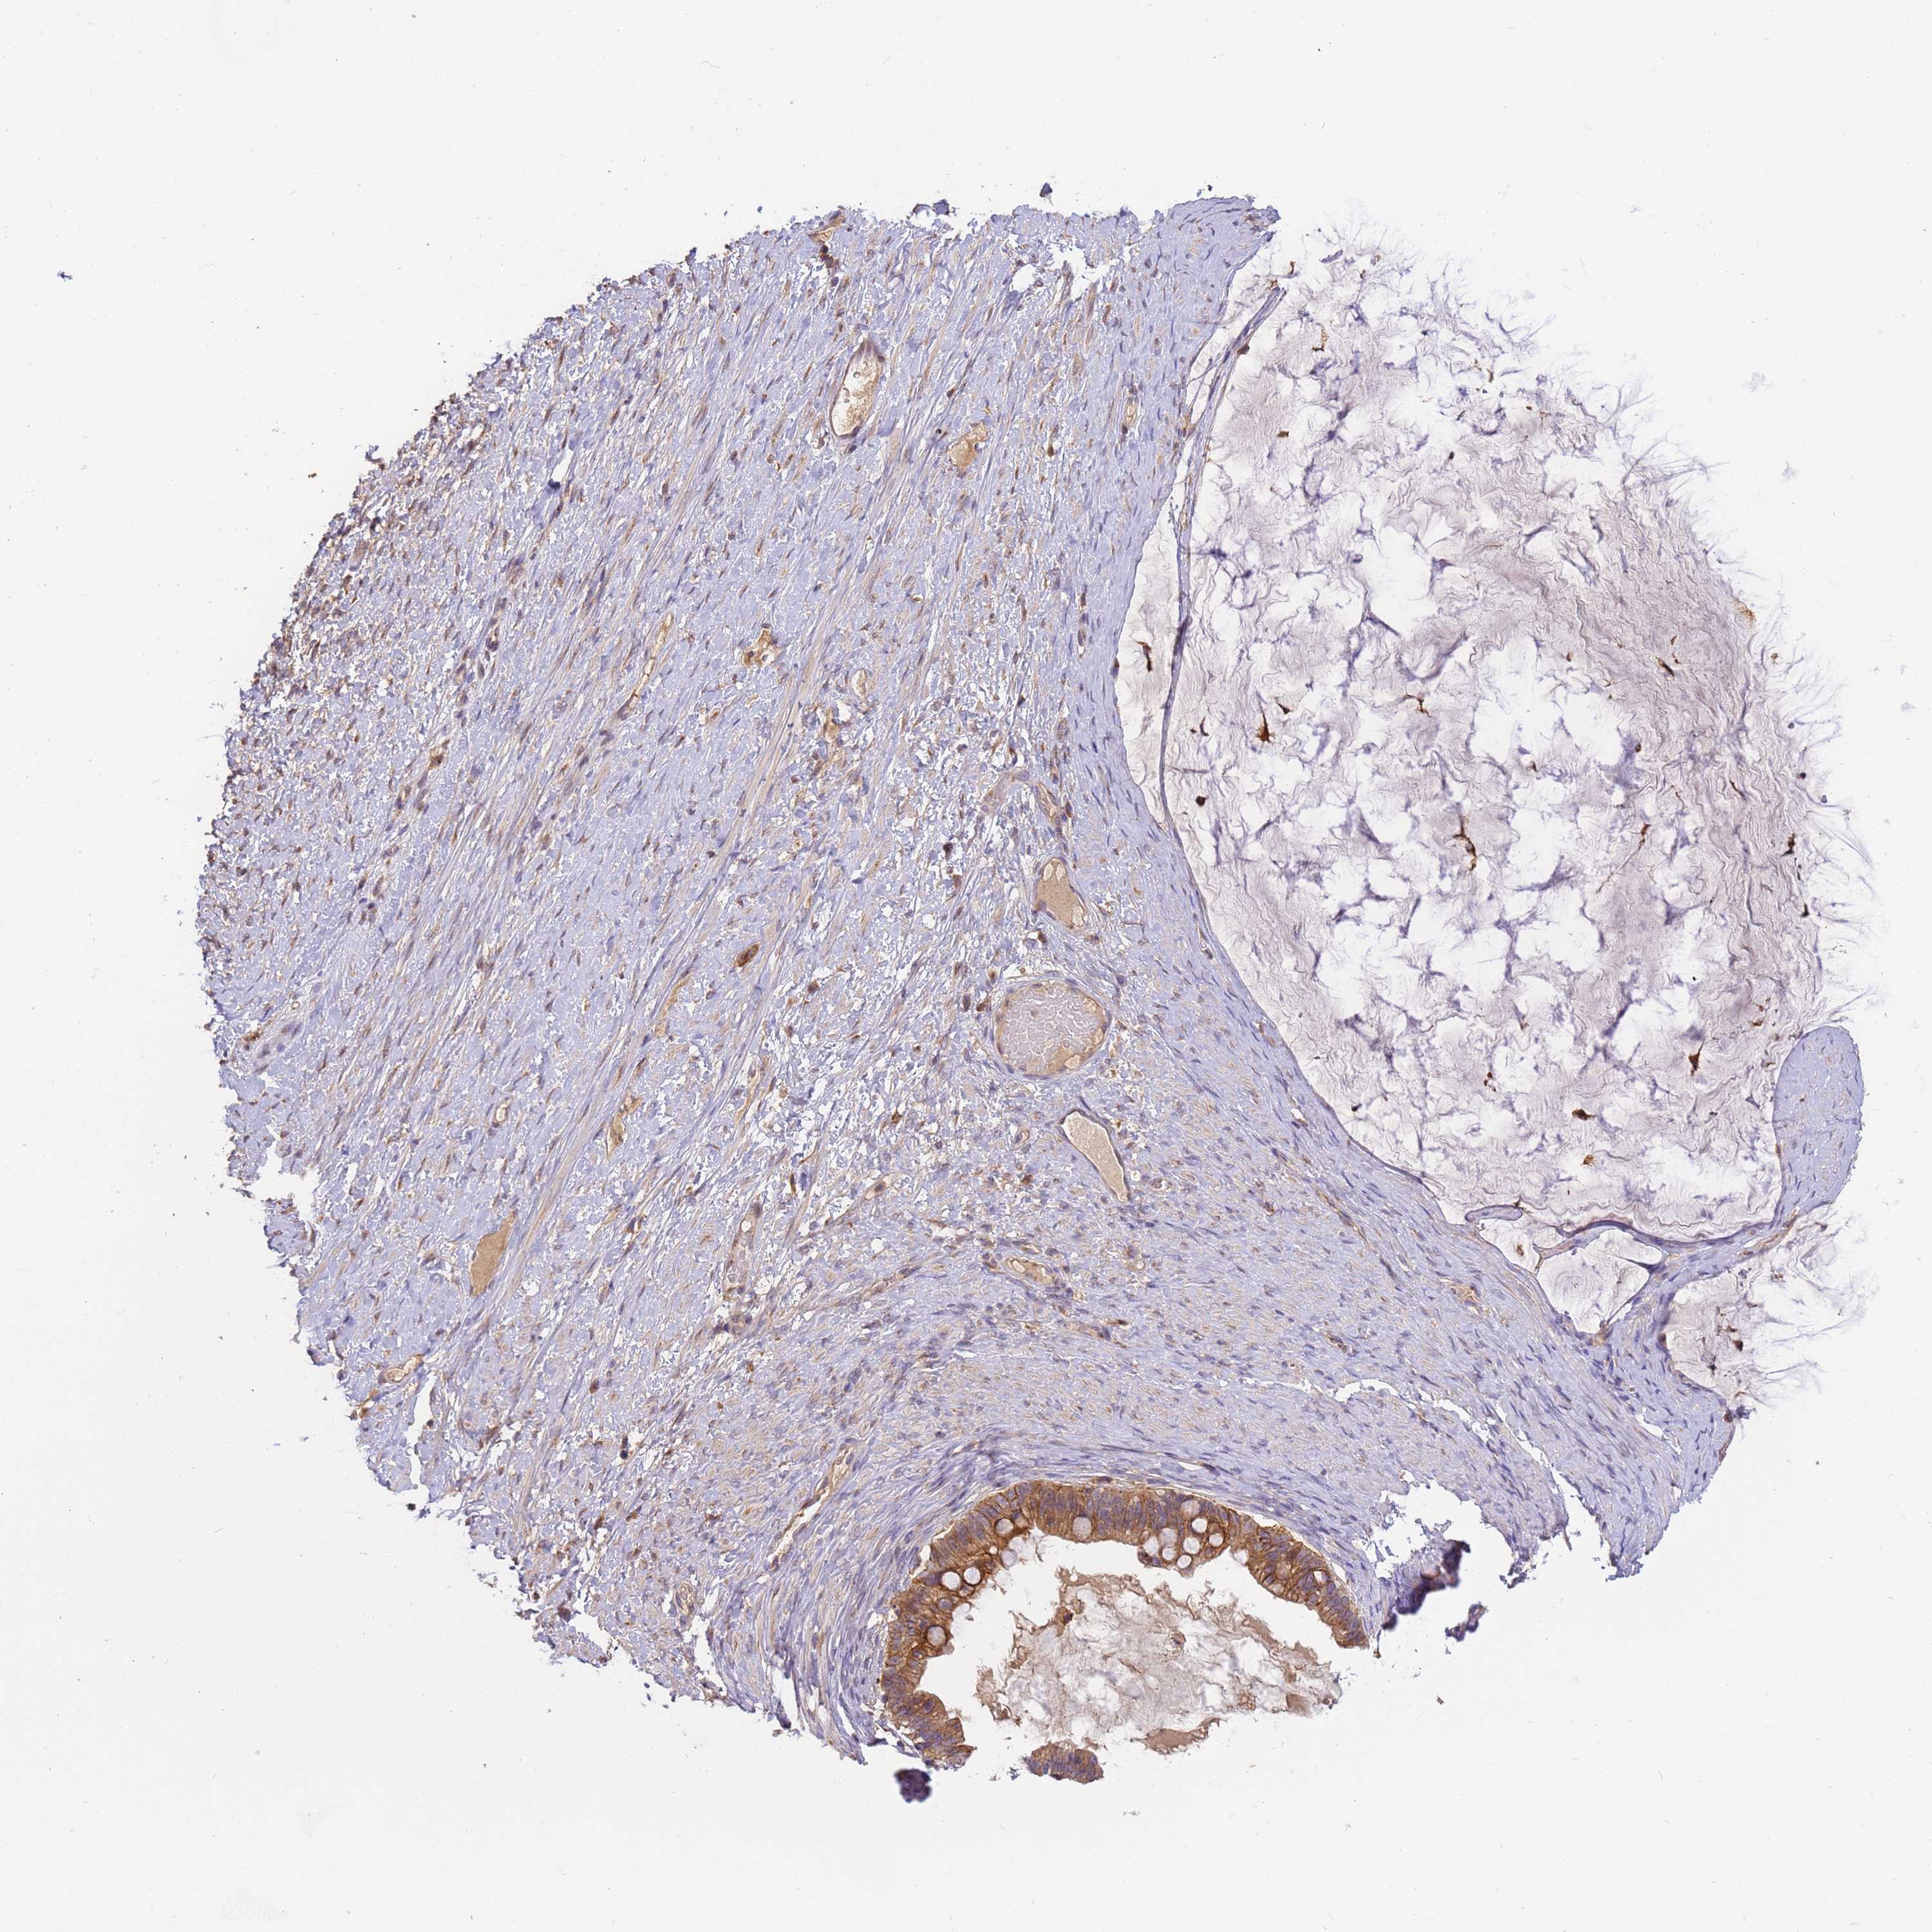

OVARIAN CANCER - Protein expressioni

A mouse-over function shows sample information and annotation data. Click on an image to view it in a full screen mode. Samples can be filtered based on level of antibody staining by selecting one or several of the following categories: high, medium, low and not detected. The assay and annotation is described here.

Note that samples used for immunohistochemistry by the Human Protein Atlas do not correspond to samples in the TCGA dataset.

Antibody stainingi

Antibody staining in the annotated cell types in the current human tissue is reported as not detected, low, medium, or high, based on conventional immunohistochemistry profiling in selected tissues. This score is based on the combination of the staining intensity and fraction of stained cells.

Each image is clickable and will lead to virtual microscopy that enables deeper exploration of all samples and also displays staining intensity scores, fraction scores and subcellular localization as well as patient and tissue information for each sample.

Antibody HPA040445

Antibody CAB034464

Staining

High

Medium

Low

Not detected

Intensity

Strong

Moderate

Weak

Negative

Quantity

>75%

75%-25%

<25%

None

Location

Nuclear

Cytoplasmic/membranous

Cytoplasmic/membranous,nuclear

Cystadenocarcinoma, mucinous, NOS